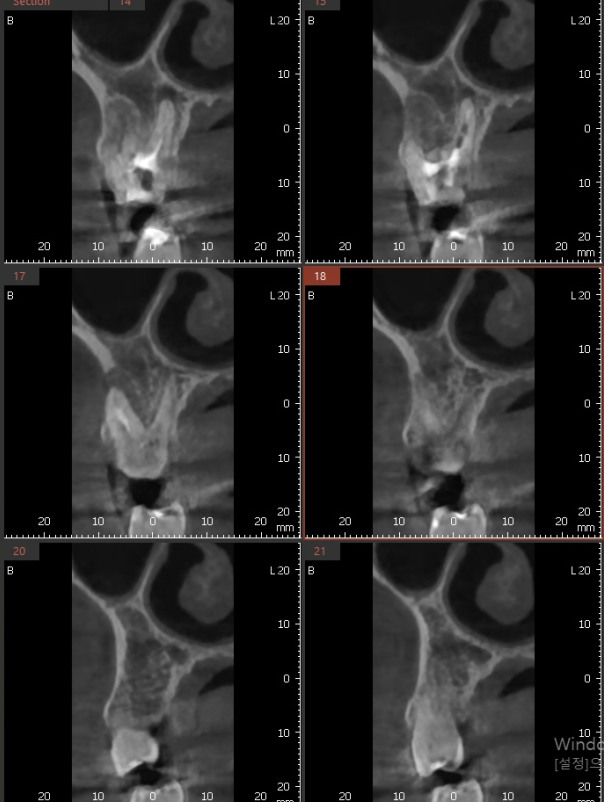

3D ct 등을 통해 정밀한 검사를 진행한 결과,

치아 뿌리 주변의 염증으로 한쪽 뼈를 녹였네요.

ct 상 한쪽 뼈만 녹아있는 상황이라

반대편 뼈에 기대해보면서